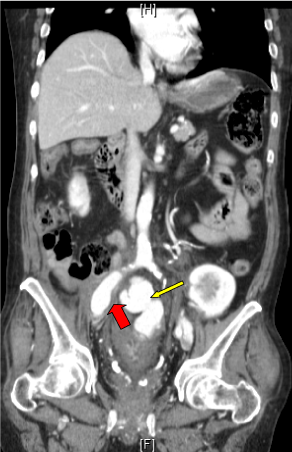

The patient remained stable and was discharged after clinical parameters were met. One month later, a flexible sigmoidoscopy was performed showing nearly complete resolution of the sub-mucosal hematoma without evidence of intraluminal blood (Figure 4A and Figure 4B). Additionally, a pelvic CT angiogram with 3-dimensional reconstruction confirmed stable location of the vascular stent graft without presence of contrast in the colonic wall (Figure 5A and Figure 5B). He was subsequently scheduled for a partial colectomy and vascular reconstruction of the right iliac artery.

Figure 5: Pelvic CT angiogram with 3-dimensional reconstruction showing in-situ vascular stent graft (red arrows) without extravasation of contrast in the colonic wall. View Figure 5